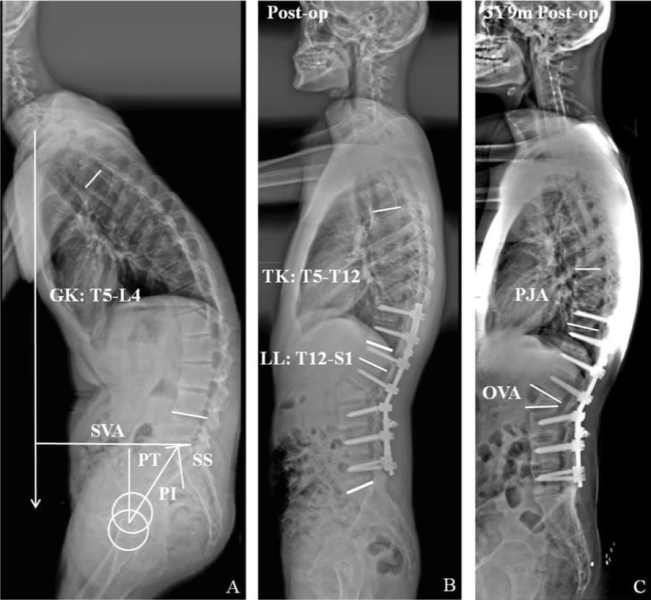

Comparar los resultados quirúrgicos entre pacientes con cifosis toracolumbar relacionada con espondilitis anquilosante (EA) con la vértebra instrumentada más baja (LIV) en S1 o superior después de una osteotomía de sustracción pedicular de un nivel (PSO).

La selección de S1 como LIV sin fijación pélvica después de PSO de un nivel en la cifosis toracolumbar causada por EA podría lograr resultados quirúrgicos satisfactorios y podría no aumentar las complicaciones. Los pacientes con desequilibrio sagital relativamente severo, pérdida de lordosis lumbar (LL), desajuste de incidencia pélvica (PI) -lordosis lumbar (LL) y pequeña pendiente sacra (SS) podrían ser los candidatos potenciales para la fusión distal a S1 después de PSO de un nivel .

Huang JC, Diao WY, Qian BP, Wang B, Yu Y, Qiao M, Qiu Y. Can fusion to S1 maintain favorable surgical outcomes following one-level pedicle subtraction osteotomy in patients with thoracolumbar kyphosis secondary to ankylosing spondylitis? Eur Spine J. 2020 Dec;29(12):3028-3037. doi: 10.1007/s00586-020-06538-w. Epub 2020 Jul 20. PMID: 32691222.